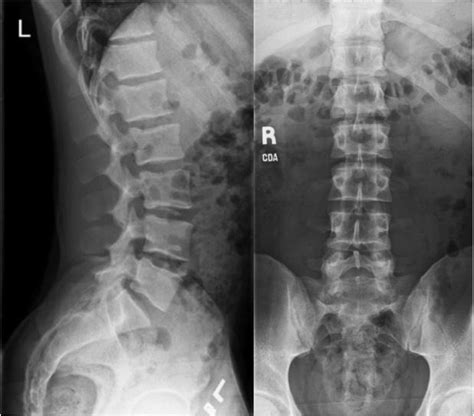

A Lower Back X Ray is a common, non-invasive imaging test that uses a small amount of radiation to create pictures of the lumbar spine. The lumbar spine consists of the five vertebrae in your lower back. By capturing these images, doctors can evaluate the bones, joints, and overall alignment of the lower spine.

Unlike more advanced imaging studies, such as an MRI or CT scan, a plain X-ray focuses primarily on dense structures like bone. While it cannot show soft tissues like nerves, discs, or muscles in great detail, it is highly effective for identifying bone-related problems that often cause chronic pain.

What Can Be Seen on a Lower Back X Ray?

While an X-ray has limitations, it is excellent at highlighting specific issues. The following table summarizes what clinicians look for when reviewing these images:

Condition What the X-Ray Shows

Fractures Disruption or cracks in the vertebrae bone.

Arthritis Narrowed joint spaces or bone spurs (osteophytes).

Scoliosis Abnormal side-to-side curvature of the spine.

Spondylolisthesis One vertebra slipping forward over the one below it.

Infections/Tumors Areas of bone destruction or abnormal bone growth.